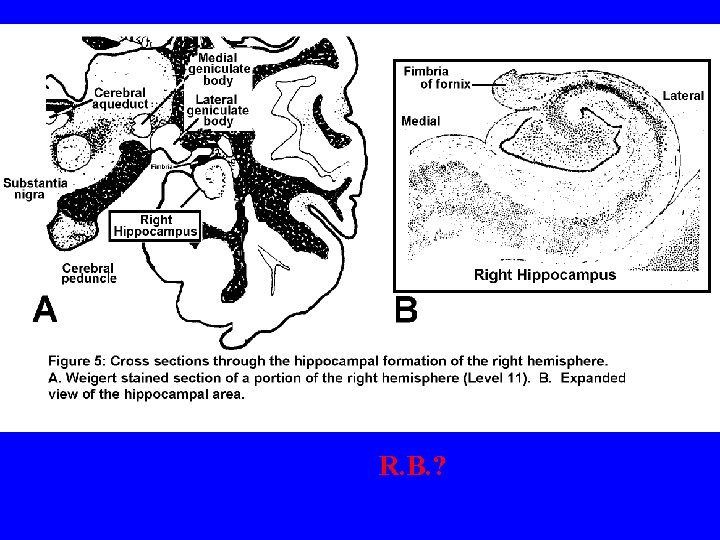

HIPPOCAMPUS • cells have receptors for cortisol that may be important in death of such cells-in moderation it increases memory • participates in explicit or declarative memory • lesion results in anterograde amnesia = loss of memories from time of damage on -patient H. M. • patient “RB” showed other closely associated brain areas involved in explicit memory-smaller lesion • loss of synapses and lots of neurofibrillary tangles and senile plaques in Alzheimer’s which leads to problems in explicit memory • cholinergic input to hippocampus is important and one source is nucleus basalis of Meynert = loss of these cells seen in Alzheimer’s (cortical NE low too in Alzheimer’s) • Hippo cells very sensitive to hypoxia